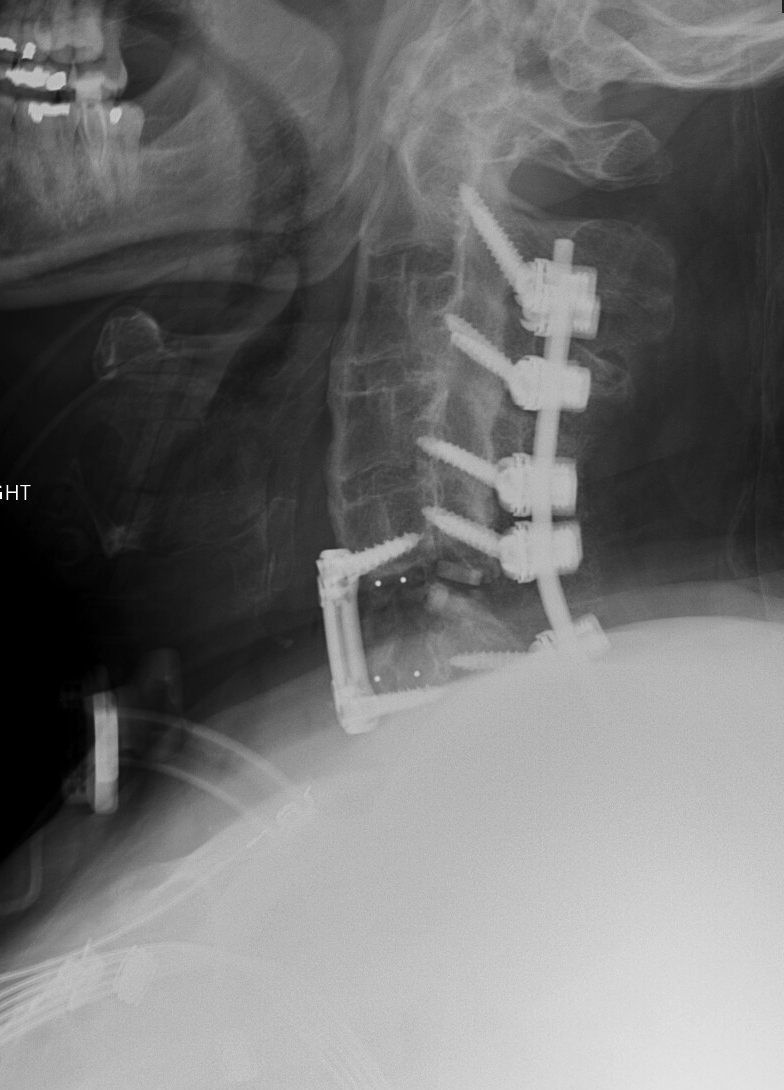

Cervical Spine Revision Surgery

Revision of a cervical spine surgery can be needed for a variety of reasons: failure for bones to fuse (cervical pseudoarthrosis), malposition or failure of implanted hardware, inadequate decompression of the spinal cord or nerve roots, new or persistent neck pain or cervical radiculopathy or myelopathy symptoms, degeneration of neighboring spinal segments, infection, spinal instability, and others.

Management options for a failed cervical surgery might include ACDF, cervical corpectomy, CORUS cervical fusion, or posterior cervical fusion, among others. Each of these options has benefits and drawbacks. The right surgery for you will depend on your symptoms, your previous surgery, the number of spinal levels affected, and factors related to your medical history, age, smoking status, and spinal anatomy.